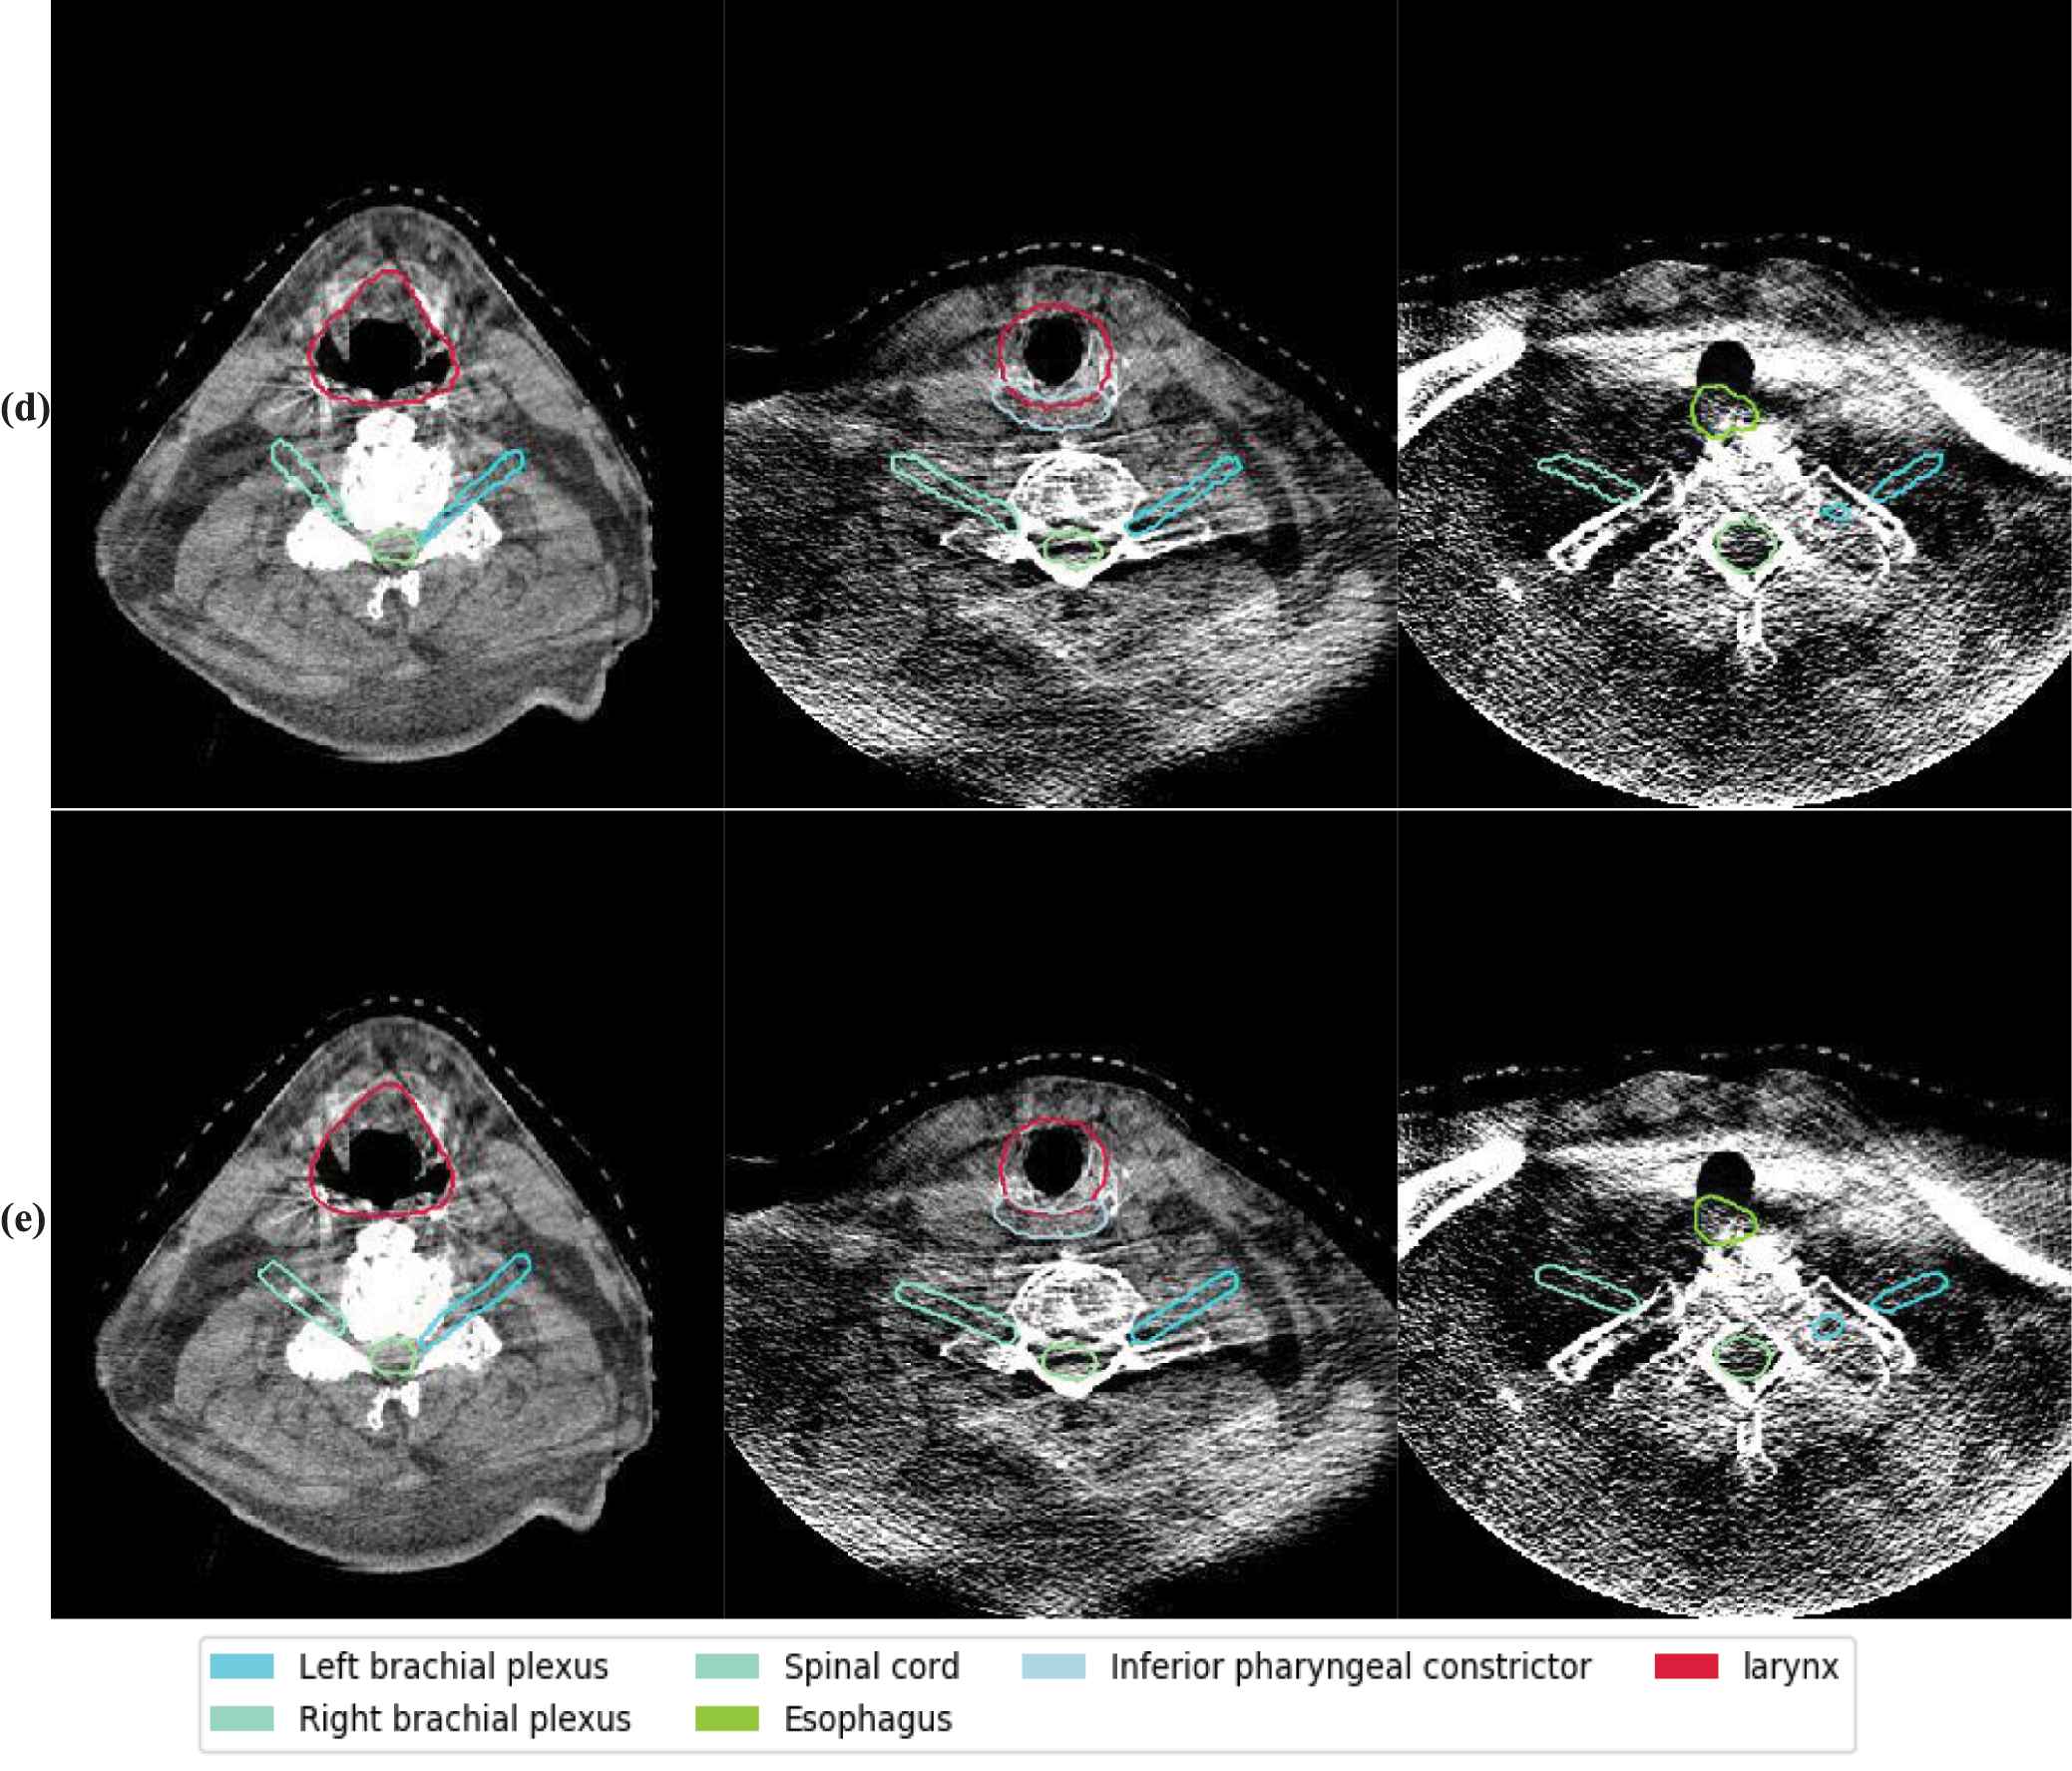

The autosegmentation results on CBCT. The background images are CBCT. The rows from top to bottom are segmentation results by different methods. Those methods are (a) Elastix, (b) Voxelmorph, (c) 5-cascaded Voxelmorph, (d) joint model and (e) ground truth for a test patient on axial view. Different colors represent different structures which are illustrated in the legend.

The quantitative evaluation results—in terms of DSC, RAVD and HD95—between the predicted and the ground truth contours of the 18 structures for 20 test patients are shown in Table 1. Our proposed method achieved DSCs of 0.61, 0.63, 0.94, 0.94, 0.75, 0.72, 0.85, 0.80, 0.81, 0.89, 0.88, 0.91, 0.92, 0.91, 0.86, 0.79, 0.78 and 0.89 for left brachial plexus, right brachial plexus, brainstem, oral cavity, middle pharyngeal constrictor, superior pharyngeal constrictor, inferior pharyngeal constrictor, esophagus, nGTV, larynx, mandible, left masseter, right masseter, left parotid gland, right parotid gland, left submandibular gland, right submandibular gland and spinal cord, respectively. We calculated paired Student t tests for all metrics for statistical analysis (Table 2). Our proposed method outperformed Voxelmorph for all the structures except left brachial plexus and right brachial plexus. When compared to 5-cascaded Voxelmorph, our proposed method performed better on brainstem, oral cavity, middle pharyngeal constrictor, mandible, left masseter, right masseter, left parotid land, right parotid gland and right submandibular gland in at least one evaluation metric. Our proposed method performed comparably to Elastix on most of the 18 structures. However, its performance was superior to Elastix on mandible, esophagus and superior pharyngeal constrictor, and inferior to Elastix on left and right brachial plexus. For visual evaluation, Figures 4 and 5 shows segmentations of two test patients from Elastix, Voxelmorph, 5-cascaded Voxelmorph, the joint model and the ground truth, where similar phenomenon can be observed.